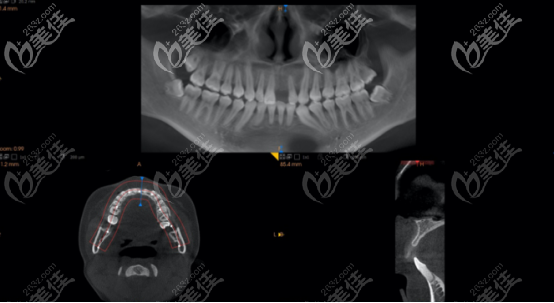

上圖是術前拍攝的ct,從圖中可以看出,嵴頂?shù)街胁抗橇扛静粔颍圆蛔阋灾畏N植體。

為什么這位患者門牙種植需要植入骨粉,原因有以下兩個:

1、當醫(yī)生分離黏膜骨膜瓣后,根據(jù)鄰牙的釉牙骨質界得出,嵴頂骨量不夠植入3.5mm的種植體。

2、用35N的扭力植入Nobel Active? 3.5×11.5植體后,表面有部分暴露,所以用了0.25gbio-oss骨粉(上圖白色為骨粉)進行填充,并且修剪成L型,然后采用無張力縫合法縫合。